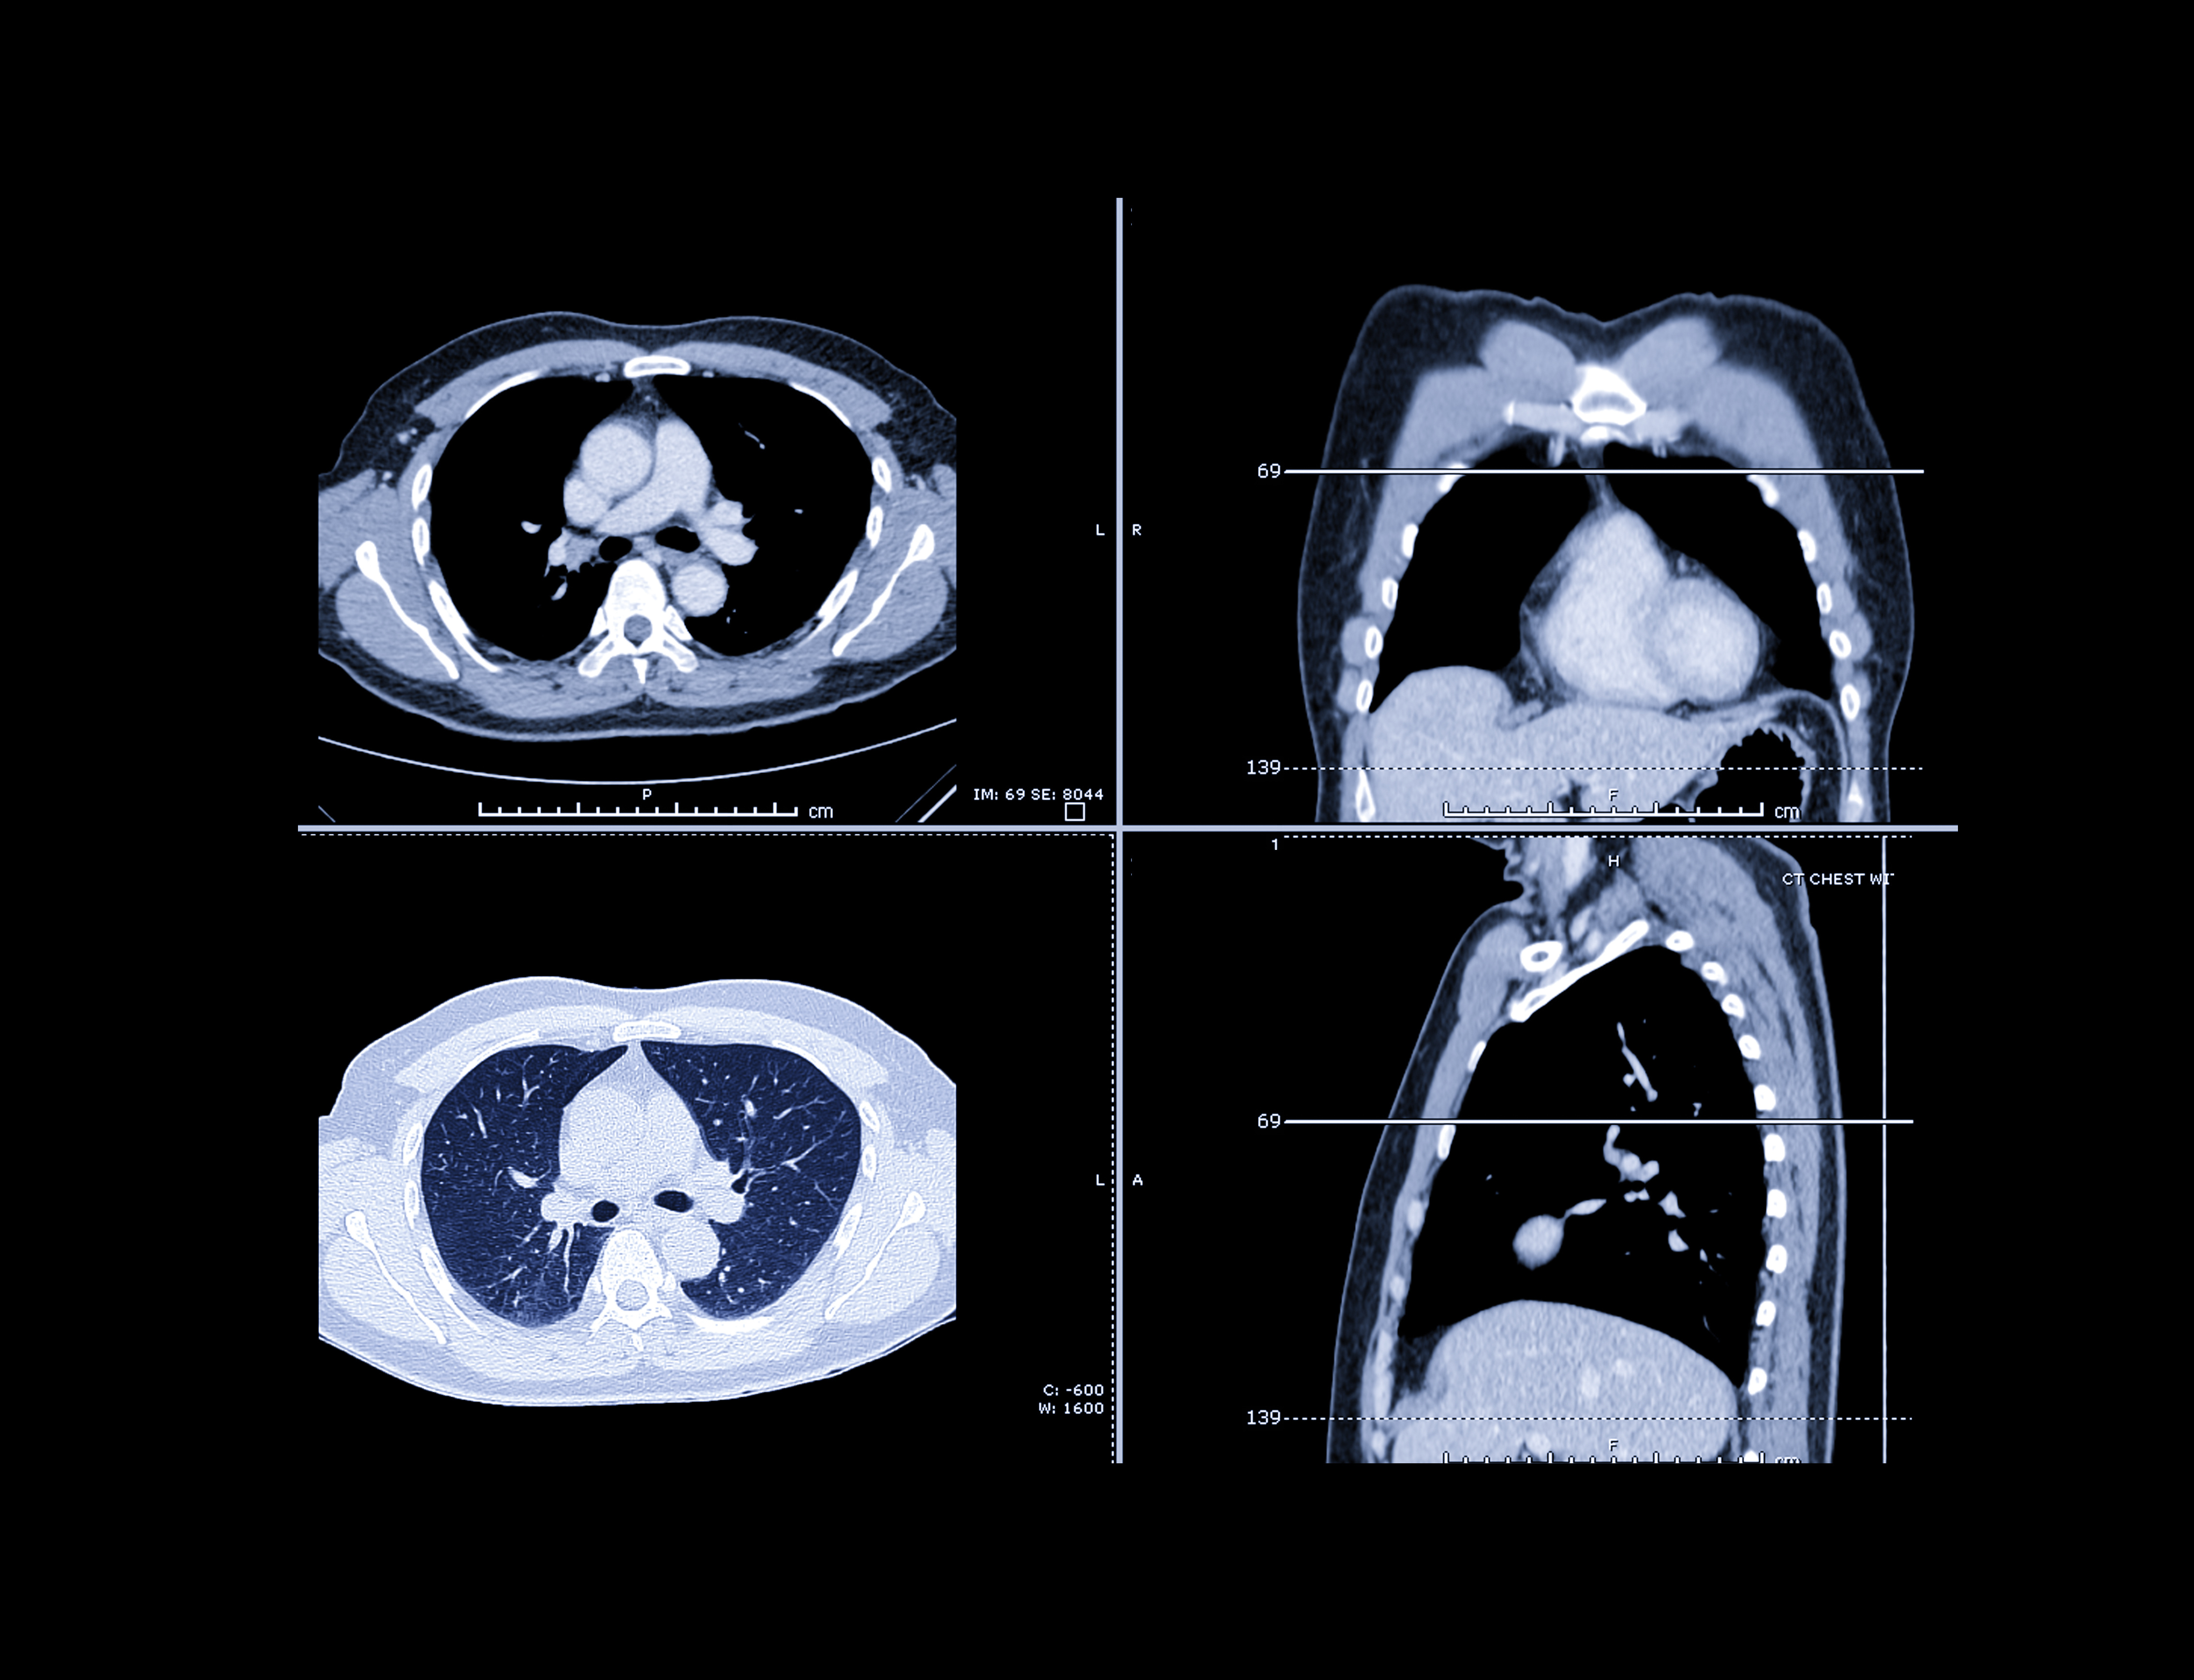

A multi-year agreement with a large Chile-based supplier of raw iodine is part of GE Healthcare’s commitment to increase the production of iodinated contrast media, commonly used in computed tomography imaging, by 30 million annually in 2025.